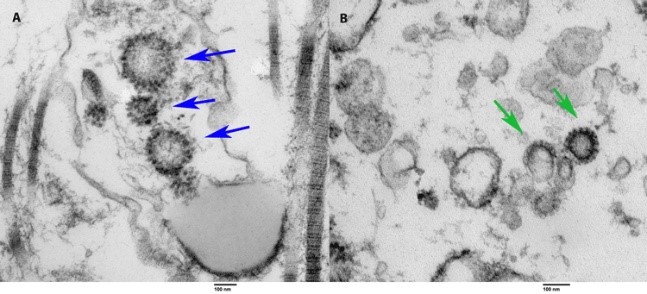

Protection From Reinfection

If we contract COVID, are we protected from reinfection? What are the chances we will contract COVID for a second time? If we have protection, how long does it last? Should previously infected people get vaccinated? We have gotten a lot of mixed messages throughout the pandemic. This study looked at how much protection having a previous COVID infection provides and gives us an idea how long the immunity may last.